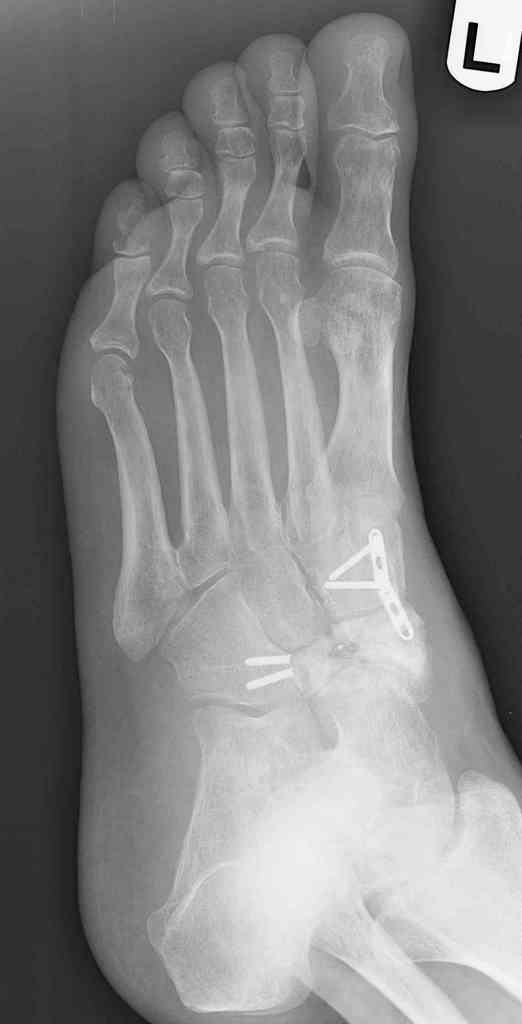

This is a 44 year old male laborer, smoker, who had his foot caught in a forklift about a year ago.

He had an ORIF and subsequent removal of hardware and presented to me with severe midfoot pain. His medial column is grossly unstable on exam but is passively correctable. Wounds are well healed, no sign of infection.

I haven't found much literature on salvage for this. What next? Iliac crest graft for structure with talo-navicular-cuneiform arthrodesis to restore the medial column? Will this fuse as an isolated procedure and given the loss of most of his subtalar motion, would a talocalcaneal arthrodesis improve his chances of fusion?